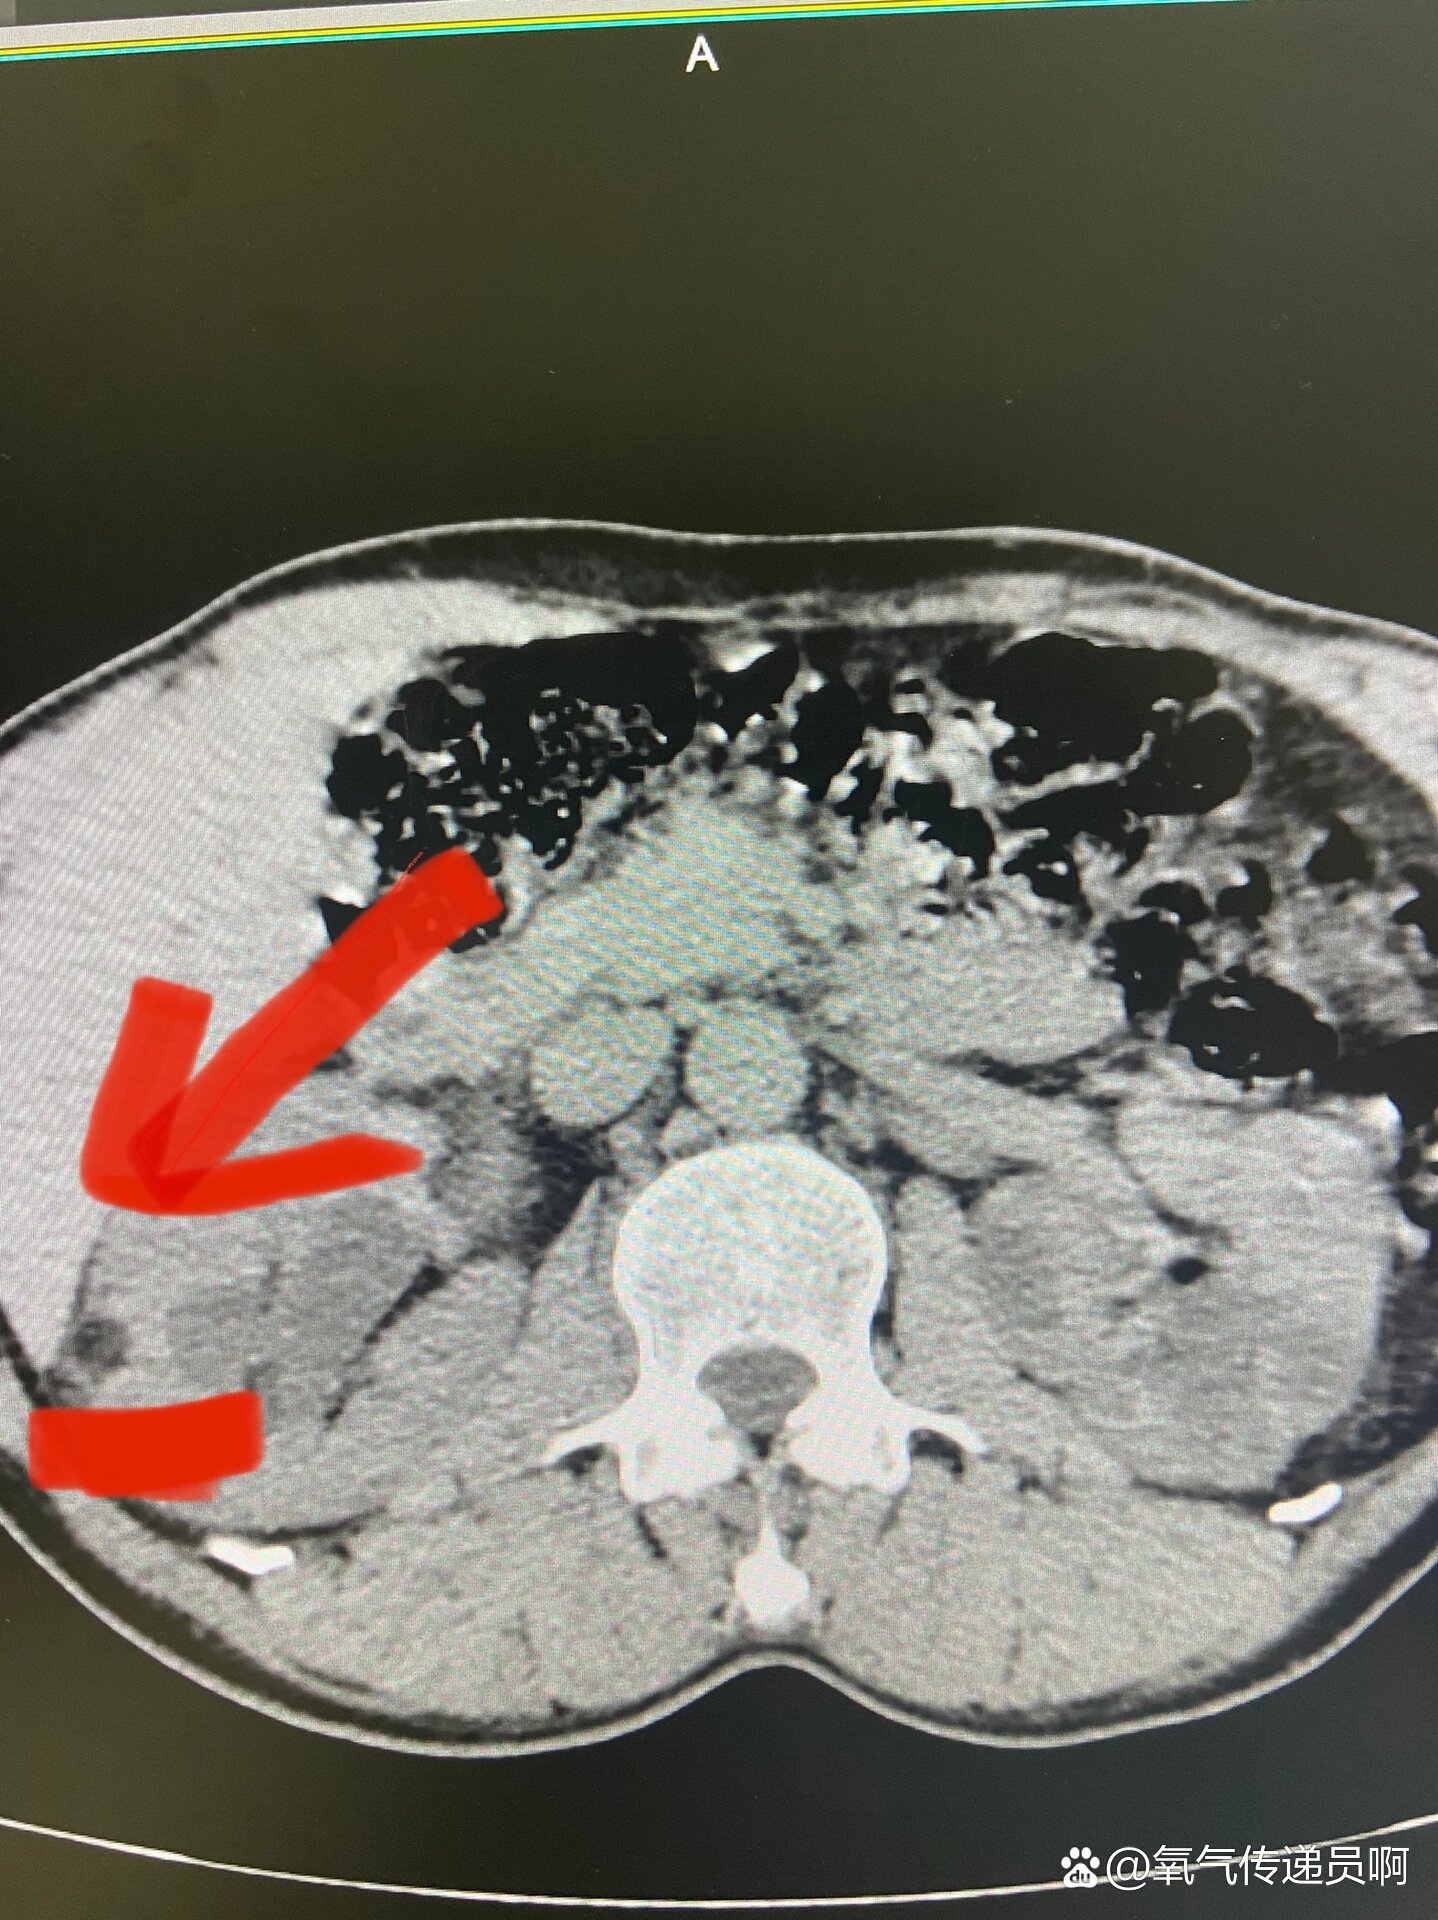

ct检查显示右肾巨大错构瘤并破裂可能,左肾肾癌